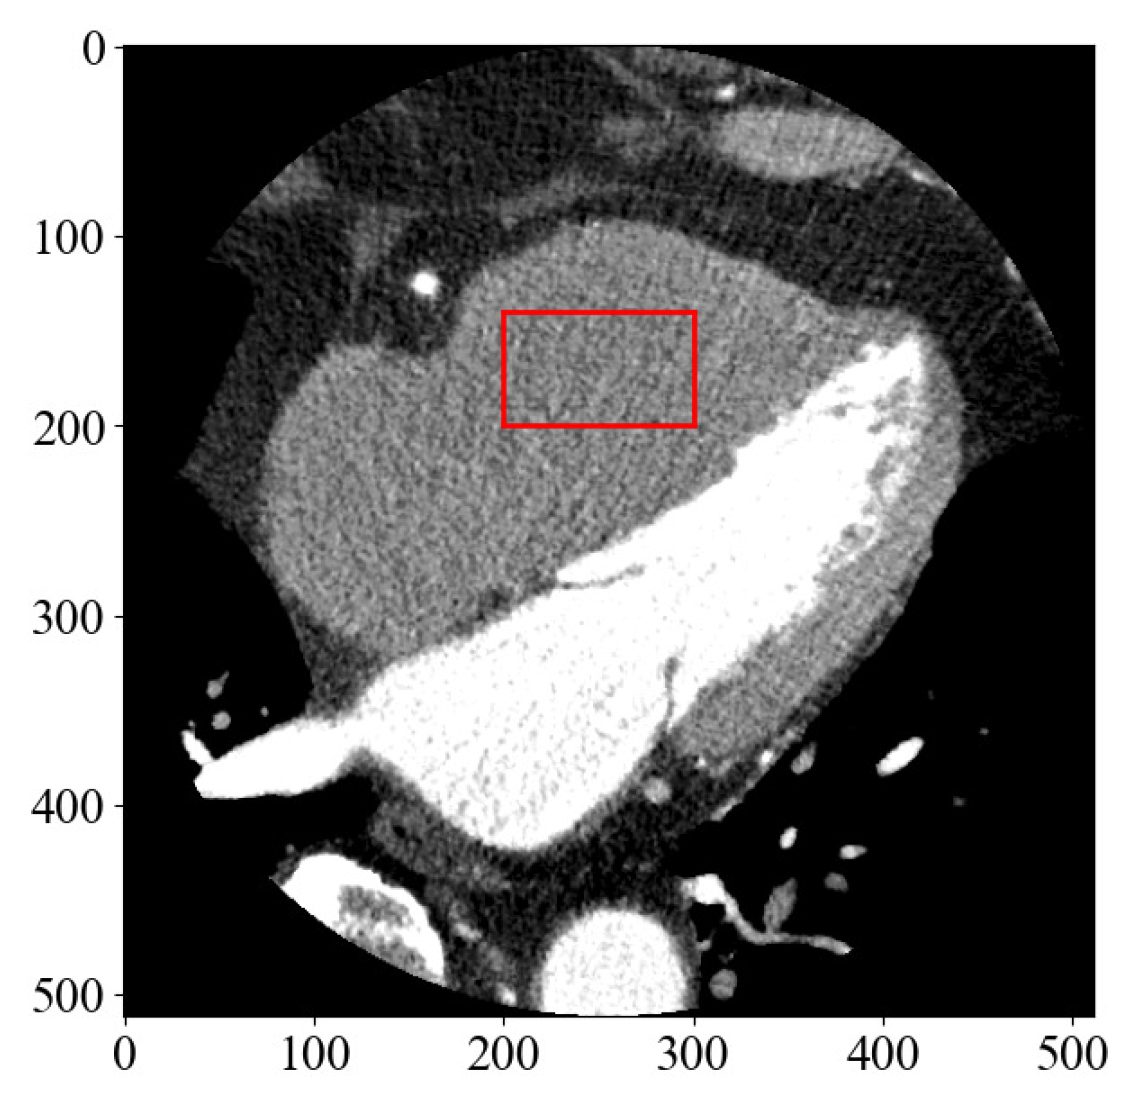

3.2. SVD Using CCTA